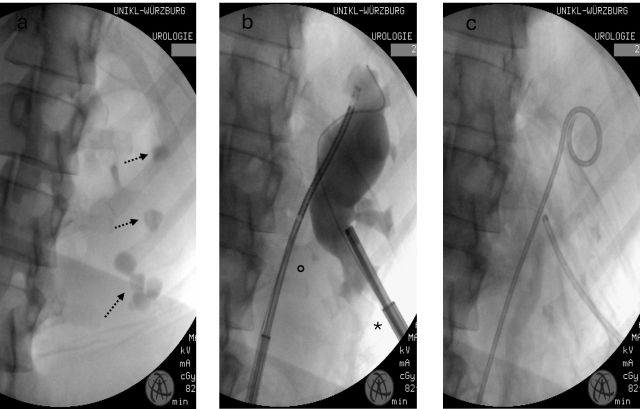

Die Durchführung der ECIRS folgt am Universitätsklinikum Würzburg einem standardisierten Protokoll. Der Patient wird in der modifizierten Valdivia-Lagerung operiert (▶ Abb. 1, 2). Anschließend erfolgt die semirigide und flex. URS mit Auffüllung des Nierenbeckens, was eine Punktion der unteren Kelchgruppe für die Mini-PNL erleichtert. Dabei wird auf eine 11/13 Ch. (Charrière) Navigator-Schleuse sowie auf ein 9 Ch. Einmalgerät zurückgegriffen. Die Mini-PNL erfolgt über einen 18 Ch. Amplatzschaft und ein 12 Ch. Nephroskop. Die Fragmentierung der Konkremente wird mittels Lumenis 120H mit MOSES™-Technologie oder der Quanta CyberHo 100 mit Virtual Basket® durchgeführt. Nach Erreichen der Steinfreiheit werden zur Abflusssicherung eine perkutane Nephrostomie (10 Ch.) sowie eine Harnleiterschiene (i. d. R. 7 Ch. Mono-J) eingelegt, welche im stationären Verlauf wieder entfernt werden. Die ▶ Abbildung 3 zeigt intraoperative Bilder, bei der zunächst multiple Konkremente in der Leeraufnahme erkennbar sind. Das letzte Durchleuchtungsbild zeigt ein steinfreies Hohlsystem mit einliegender perkutaner Nephrostomie und Mono-J-Harnleiterschiene.